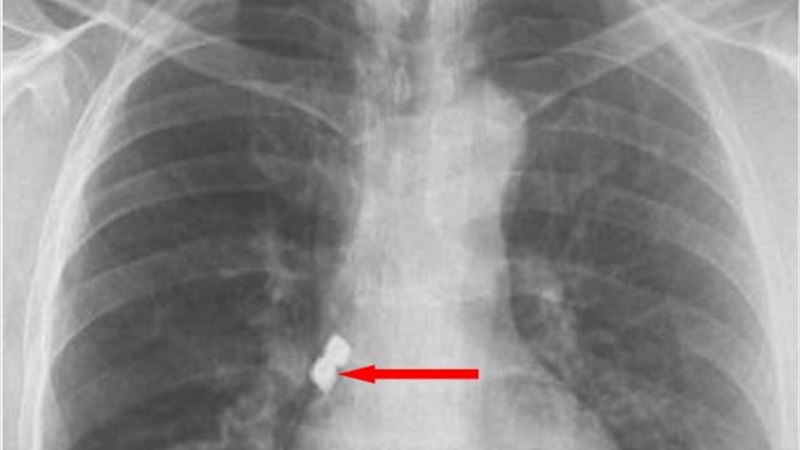

Nefes almakta zorlanan Kaplan, Emirdağ Devlet Hastanesinde yapılan ilk müdahalenin ardından Afyonkarahisar'da başka bir hastaneye sevk edildi.

Kaplan'ın akciğer girişinden implantlar başarıyla çıkarıldı.